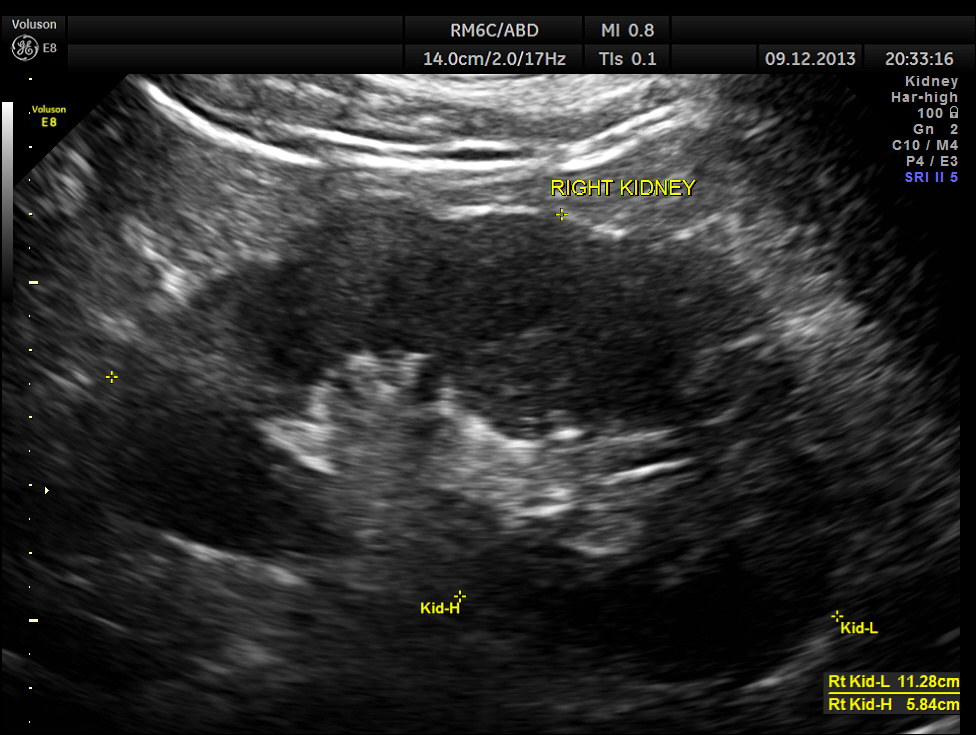

This patient was being evaluated for painless hematuria.

His right kidney appeared normal.